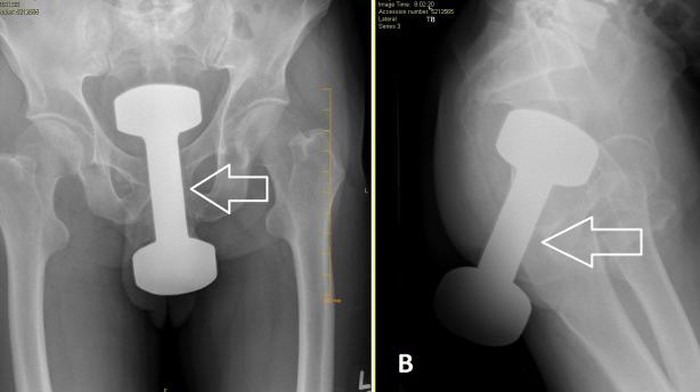

Jakarta – Viral penampakan sinar-X barbel yang masuk ke area dubur. Dalam gambar tersebut, terlihat jelas sebuah barbel yang tersangkut di area selangkangan.

Setelah ditelusuri, kasus barbel nyangkut di anus itu tercatat di jurnal internasional Cureus berjudul Successful Retrieval of a Retained Rectal Foreign Body in the Emergency Department. Kondisi itu dialami seorang pria berusia 50 tahun dengan gejala nyeri perut bagian bawah.

Kasus tersebut tercatat pada Januari 2018. Bukan di Indonesia, dumbell nyangkut di dubur itu terjadi di Amerika Serikat dan ditangani oleh dokter yang bekerja di Guthrie Robert Packer Hospital, Pennsylvania, Amerika Serikat. Pasien juga telah memberikan persetujuan untuk memuat hasil x-raynya di jurnal tersebut.

Dokter yang menangani pria itu menemukan barbel seberat 2 kg yang tersangkut di duburnya. Pakar menyebut benda itu sengaja dimasukkan demi kepuasan seks.

Tak menunggu lama, dokter langsung melakukan prosedur untuk mengeluarkan benda asing itu dari duburnya. Beruntung, dumbell itu berhasil dikeluarkan tanpa harus operasi besar.